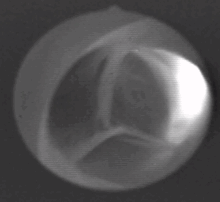

Frontal view of the Aortic valve

The aortic valve is a valve in the human heart between the left ventricle and the aorta. It is one of the two semilunar valves of the heart, the other being the pulmonary valve. The heart has four valves and the other two are the mitral and the tricuspid valves. The aortic valve normally has three cusps or leaflets, although in 1–2% of the population it is found to congenitally have two leaflets.[1]

The aortic valve normally has three cusps – a left, right and posterior cusp.[2]